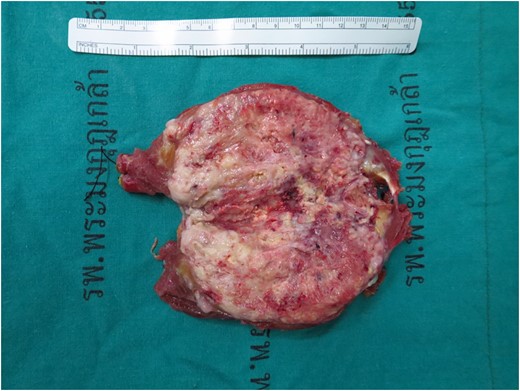

Gross specimen, tumor size 11.5 cm × 5.0 cm × 5.0 cm, a poorly circumscribed, large gray–yellow mass with semi-soft tan homogenous cut surface with large areas of hemorrhage and necrosis.

The specimen consists of an 11.5 cm × 5.0 cm × 5.0 cm ovoid-shaped fragment of pink–red soft tissue with orienting sutures present. Skeletal muscle is present at one margin and the opposite margin is smooth pink–yellow and glistening. Sectioning reveals a poorly circumscribed, large gray–yellow mass with semi-soft tan homogenous cut surface with large areas of hemorrhage and necrosis of nonspecific appearance (Fig. 4). The mass measures ~8.5 cm × 4.8 cm and grossly abuts all surgical margins with a thin capsule separating it from the resection margins.